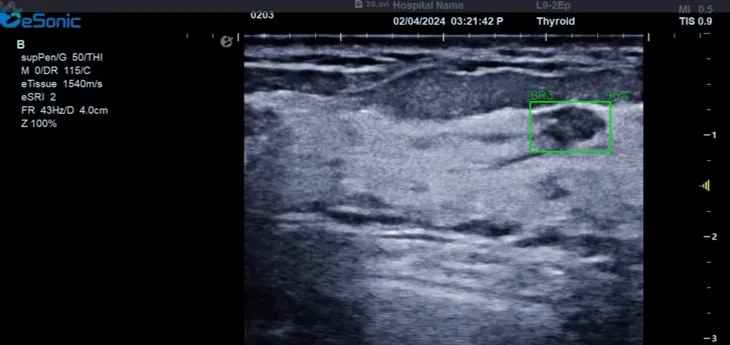

对于乳腺结节相关的自动检测功能,乳腺结节病灶检出率≥95%、良恶性分类灵敏度≥90%、良恶性分类特异度≥85%。